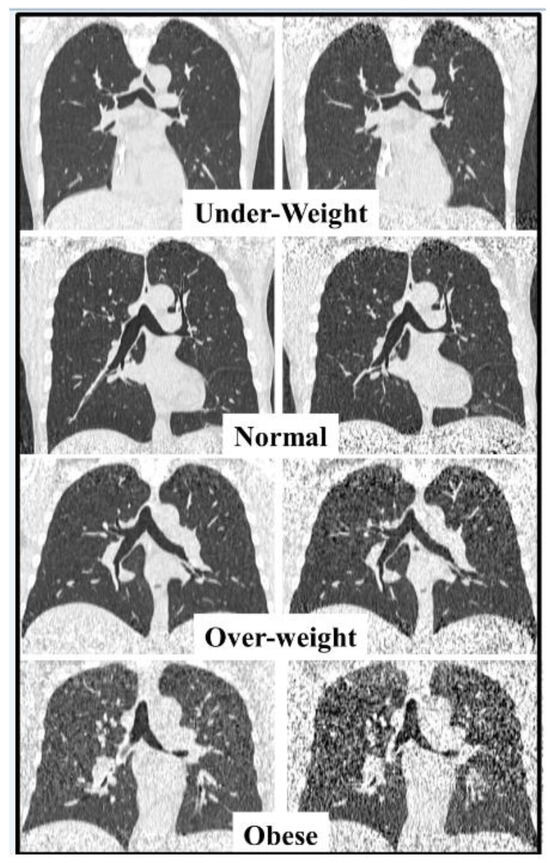

| All | Underweight | Normal | Overweight | Obese | |

|---|---|---|---|---|---|

| Number of patients | 100 | 5 | 46 | 28 | 21 |

| Male/Female | 53/47 | 3/2 | 26/20 | 16/12 | 8/13 |

| Age (years) | 55.3 ± 14.7 [18–80] | 51.4 ± 18.6 [22–69] | 55.3 ± 15.8 [19–80] | 56.3 ± 13.1 [27–74] | 55.1 ± 15.0 [18–76] |

| BMI a (kg/m2) | 26.2 ± 6.3 [14.7–60.2] | 16.5 ± 1.6 [14.7–18.2] | 22.6 ± 1.4 [19.8–24.9] | 27.1 ± 1.5 [25.1–29.4] | 34.0 ± 3.8 [30.0–44.6] |

| LDCT DLP a (mGy × cm) | 125.7 ± 18.9 [85.5–160.8] | 123.8 ± 21.7 [93.9–148.5] | 123.2 ± 21.5 [85.5–158.3] | 125.2 ± 17.4 [95.7–160.8] | 132.0 ± 12.9 [100.6–150.7] |

| uLDCT DLP a (mGy × cm) | 30.5 ± 4.7 [20.6–39.1] | 30.0 ± 5.4 [22.7–36.1] | 29.9 ± 5.3 [20.6–38.5] | 30.4 ± 4.3 [23.1–39.1] | 32.1 ± 3.2 [24.3–36.7] |

| LDCT Effective a Dose (mSv) | 1.76 ± 0.26 [1.20–2.25] | 1.73 ± 0.30 [1.31–2.08] | 1.73 ± 0.30 [1.20–2.22] | 1.75 ± 0.24 [1.34–2.25] | 1.85 ± 0.18 [1.41–2.11] |

| uLDCT Effective a Dose (mSv) | 0.43 ± 0.07 [0.29–0.55] | 0.42 ± 0.08 [0.32–0.51] | 0.42 ± 0.07 [0.29–0.54] | 0.43 ± 0.06 [0.32–0.55] | 0.45 ± 0.04 [0.34–0.51] |